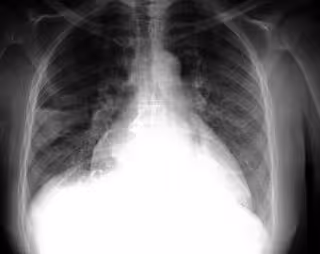

FLICKR/PULMONARY PATHOLOGY/CC BY-SA 2.0 - Archivo